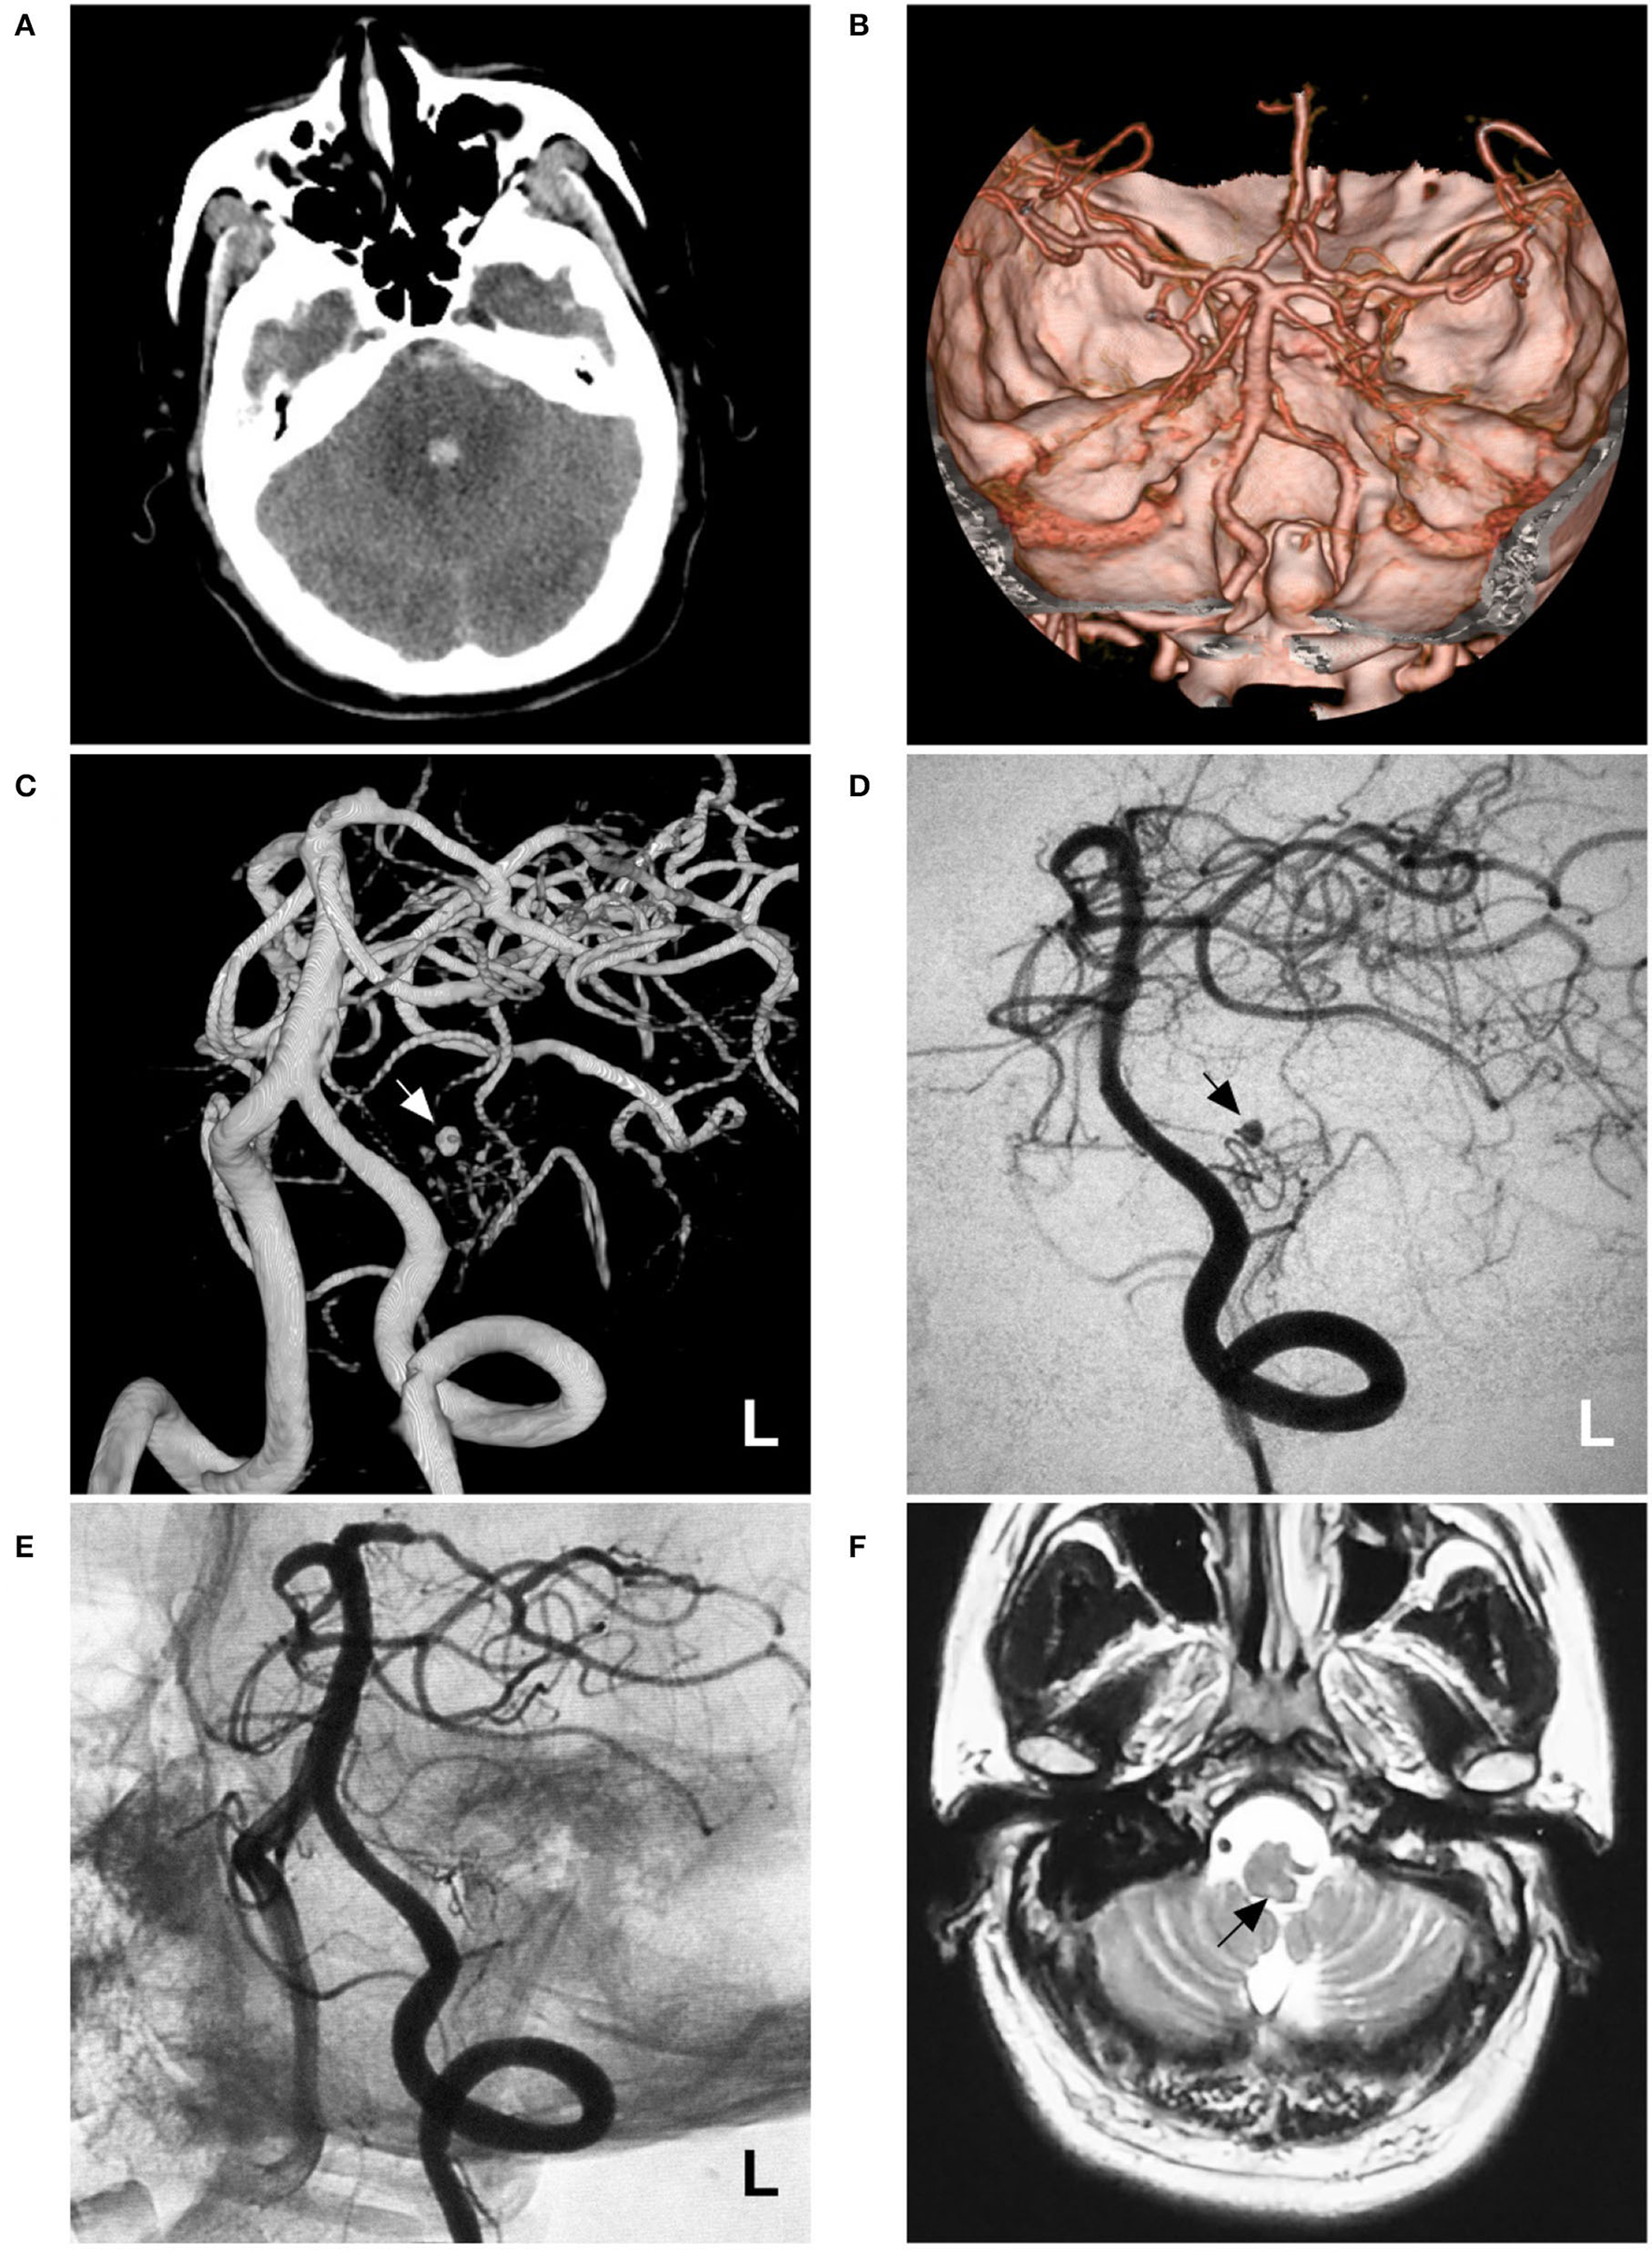

A 53-year-old male suffered a sudden severe headache and vomited 4 h before admission. He was a Chinese patient of Han nationality who was healthy and denied having a history of chronic diseases. He had no history of drug abuse or surgical treatment of craniocerebral disease. Upon admission, a physical examination was performed, and the results were unremarkable, except for nuchal rigidity. Head CT showed subarachnoid hemorrhage (SAH) concentrated at the perimesencephalic cistern with involvement of the fourth ventricle (Figure 1A). CT angiography (CTA) revealed no underlying vascular lesions (Figure 1B). Catheter angiography revealed that the left PICA was hypoplastic and plexiform. Several small arteries originated from the left vertebral artery (VA) near the origin of the PICA. A pseudoaneurysm was located in the hypoplastic and plexiform PICA (Figures 1C,D). His family had no similar diseases.

Imaging of case 1. (A) CT shows subarachnoid hemorrhage concentrated at the perimesencephalic cistern with involvement of the fourth ventricle. (B) CTA reveals no underlying vascular lesions. (C,D) Angiograms of the left VA show a pseudoaneurysm (arrow) located in the hypoplastic and plexiform PICA. (C) shows a three-dimensional angiogram, and (D) shows a two-dimensional angiogram. (E) Angiogram of the left VA shows that the aneurysm and parent PICA are cast with Onyx, and other branches are visualized. (F) Follow-up MRI scan shows a minor brainstem infarction (arrow). CT, computed tomography; CTA, CT angiography; L, left; MRI, magnetic resonance imaging; PICA, posterior inferior cerebellar artery; VA, vertebral artery.

Occlusion of the aneurysm and parent PICA via EVT was planned under general anesthesia. During the procedure, a Marathon microcatheter (Medtronic, Irvine, California, USA) was introduced into the PICA via the guidance of a microwire to access the aneurysm as much as possible. Then, the aneurysm and parent PICA were occluded with an Onyx liquid embolic system (Medtronic, Irvine, California, USA) (Figure 1E). Postoperatively, he showed no consciousness or movement disturbance. Mild hoarseness, dysphagia, and left central facial paralysis were noticed. The patient was discharged 1 week later. On follow-up one and a half years later, he recovered significantly, except for mild hoarseness. MRI only revealed the old brainstem infarction (Figure 1F).